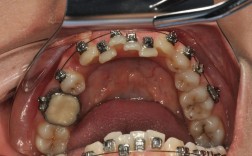

虽然阻抗中心是牙齿的固有属性,但正畸治疗中通过矫治器(如托槽、带环)施加的力的大小、方向及作用点(施力点),会改变牙齿实际移动的“等效阻抗中心”,当托槽位置过高(靠近切缘)时,施力点偏离天然阻抗中心,牙齿易发生倾斜移动而非整体移动;若通过额外装置(如舌侧扣、种植体支抗)调整施力点,使其通过天然阻抗中心,则可实现更高效的整体移动。